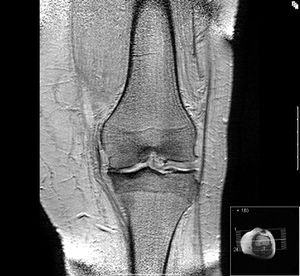

NMR-Bild einer medial betonten Kniearthrose, von vorne gesehen